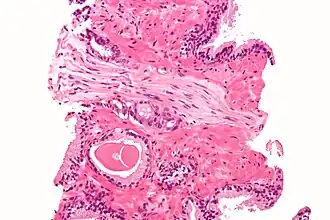

Cross-section of a nerve

Micrograph demonstrating perineural invasion of prostate cancer. H&E stain.

Cancer can spread by invading the spaces around nerves. This is particularly common in head and neck cancer, prostate cancer and colorectal cancer. Multiple sclerosis is a disease associated with extensive nerve damage. It occurs when the macrophages of an individual's own immune system damage the myelin sheaths that insulate the axon of the nerve.